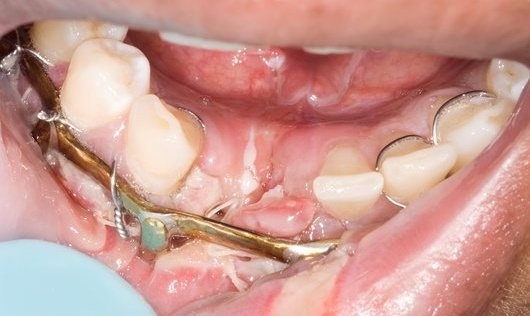

Photos of Archbars that have been wired to teeth. Elastics or wires are used to bring the archbars (and hence, teeth and jaws) together.

Arch-bars, Leonard Buttons and IMF Screws are used to support and stabilise fractured jaws, both stabilising the jaw and the opposing jaw.

With elastics between the upper and lower jaw, it is hoped that the teeth and the way they are aligned and bite together will also correct.